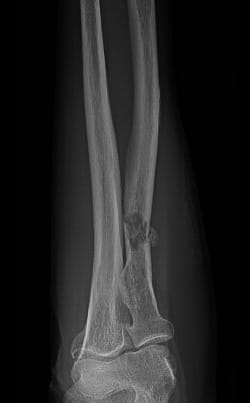

X-ray image showing cancer cells spreading to bone

Skeletal Metastasis: When cancer cells spread to bone (metastasize), our surgeons offer a variety of surgical and nonsurgical procedures to diagnose, treat and lessen the pain of fractures caused by the underlying disease.